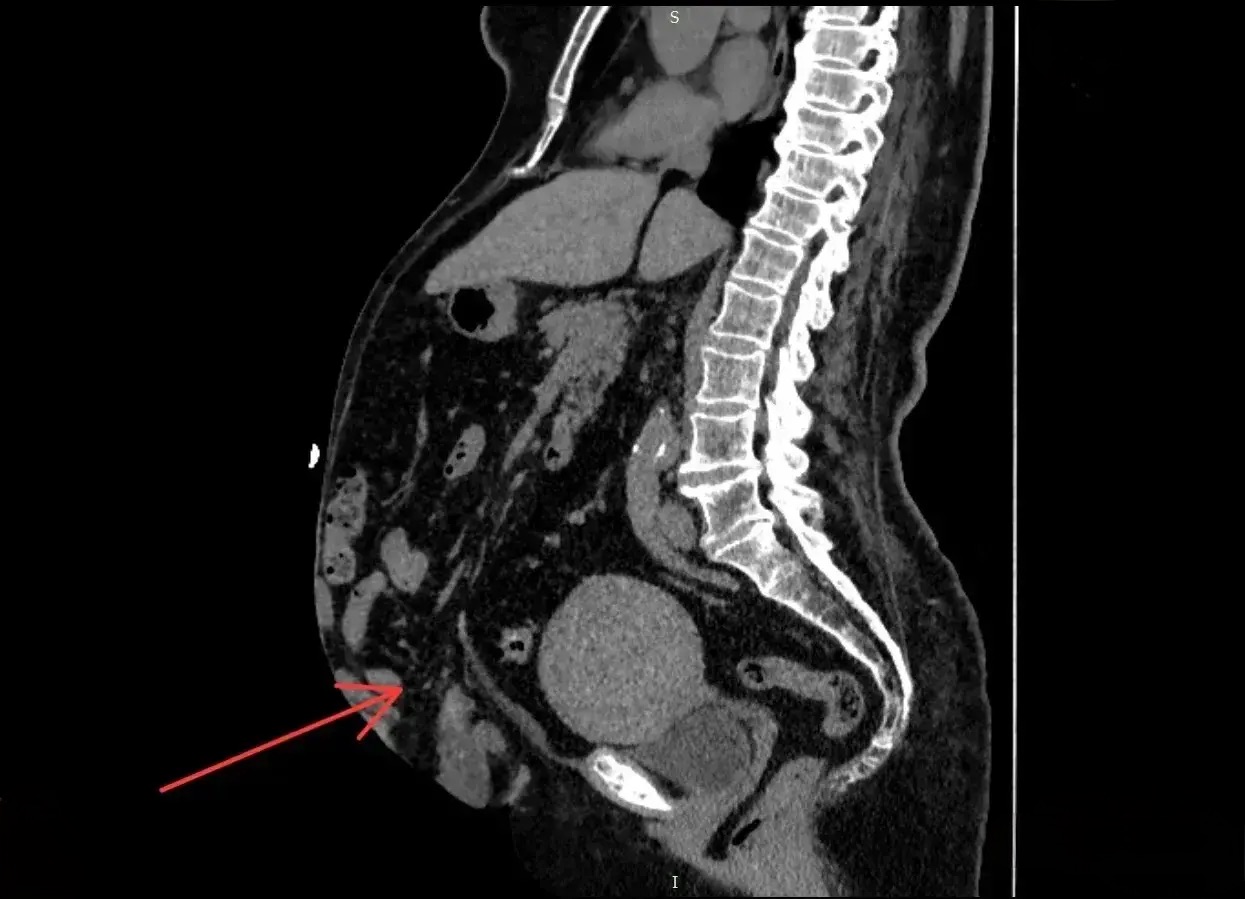

Компьютерная томография выявила, что объем грыжи составил 41% брюшной полости. Такое состояние в медицине называют потерей домена.